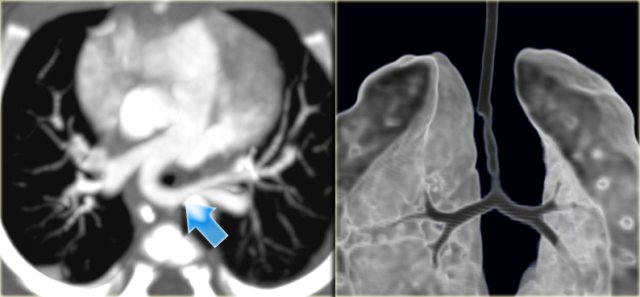

Right Arch with Aberrant left subclavian Right Arch with Aberrant left subclavian

On the left images of a symptomatic child.

On the axial image there is a right arch with the left subclavian artery that comes off on the posterior side and runs behind the trachea and the esophagus.

The compression of the trachea is demonstrated on the volume rendered view.